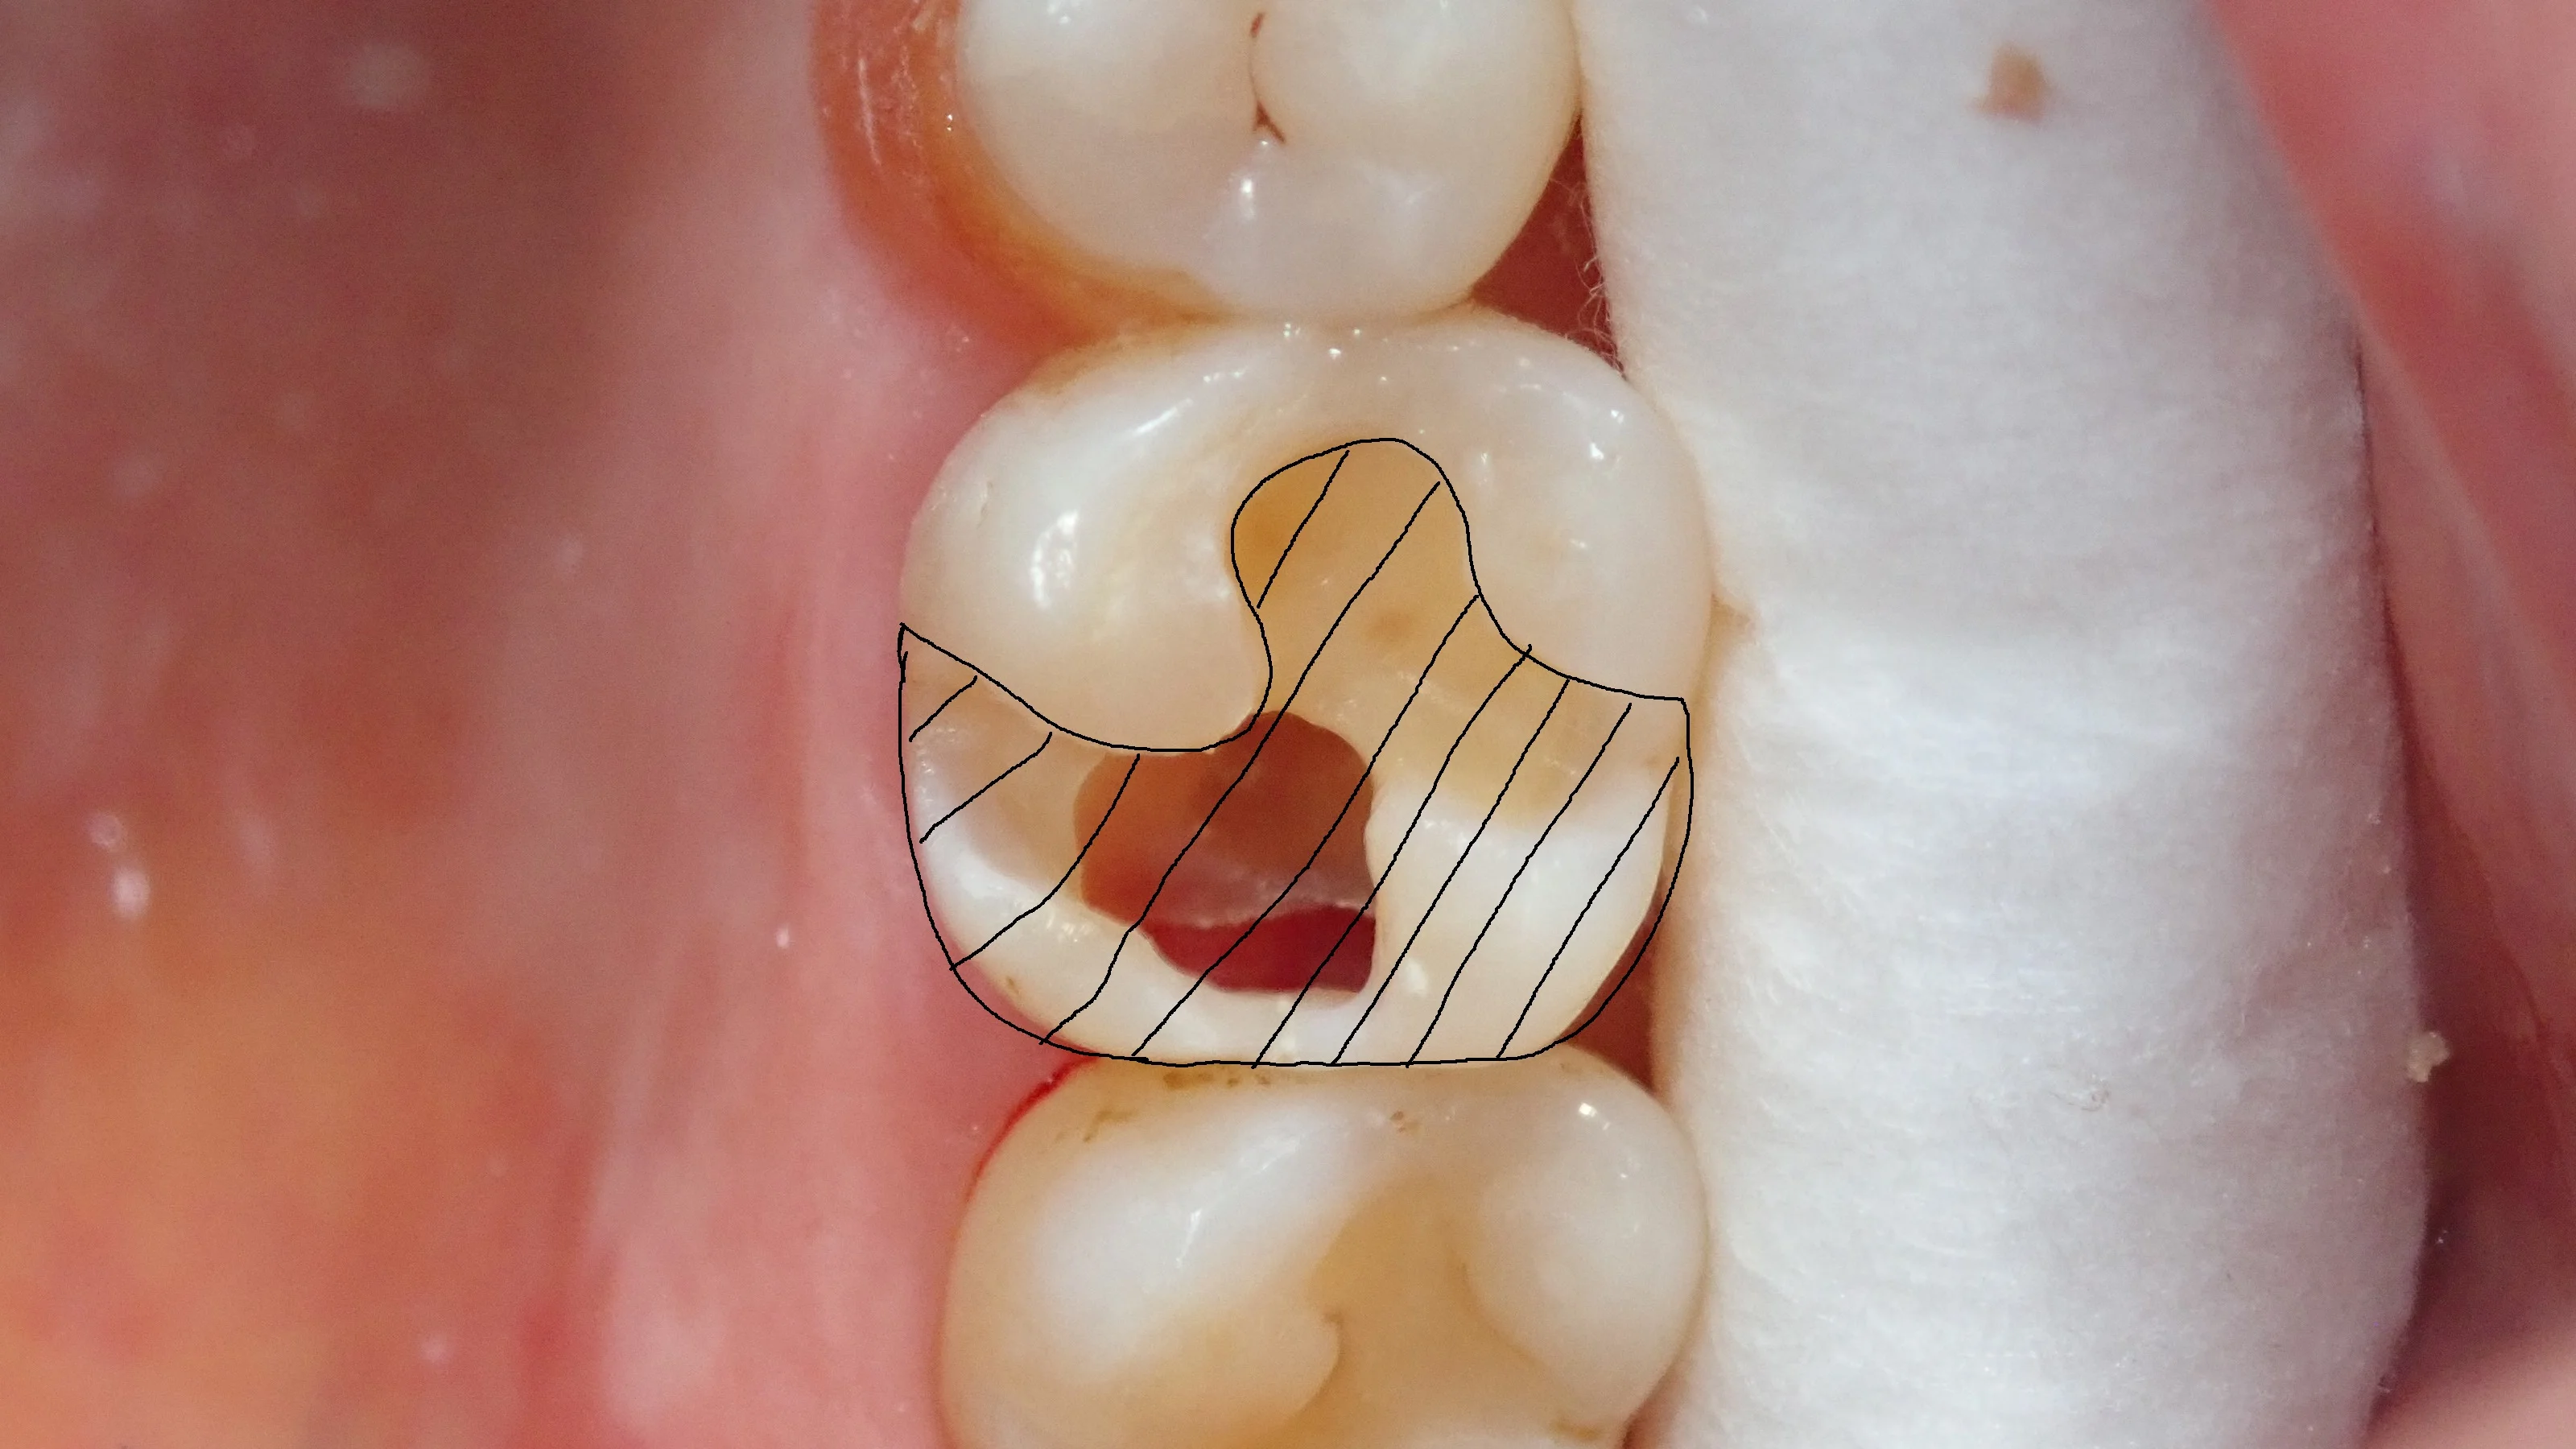

そして、仮封材を除去した画像がこちらです。

実際、画像の下半分は中身が殆どない状態です。

神経もうっすら見えており、歯茎が虫歯の穴から見えている状態。

本当にギリギリの状態だったんです・・・。

ちなみに、これ、従来の治療(メタルインレー・セラミックインレー)で治そうとすると・・・

こんな感じで、歯のほとんどを削り取る羽目になります。

今回は、

・歯の表層をうまく残すことが出来た

・歯茎と歯の間に入れる器具が綺麗に入れることが出来、確実に処置を行うことが出来た

・重要な部分の歯は残せているので、強度的にも問題なし

・インレーにすると歯を大きく失ってしまう事となる

ということで、

自費のセラミックインレーや保険のメタルインレーよりも予後が良く、予知性の高い治療と考えられるダイレクトボンディングを治療法の一つとして提示しました。

ご本人からも「なるべく歯を残してほしい」との要望がありましたので、表題の通り、ダイレクトボンディングで行うこととなりました。